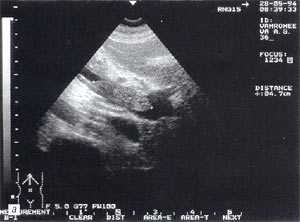

Свободная жидкость в брюшной полости - отмечена в 18% случаев (рис. 4), из них 80% у мужчин и 20% у женщин. Жидкость в объеме до 100 мл определяется только в одной анатомической области ( чаще в малом тазу), более 100 мл - по боковым каналам и в других отделах брюшной полости. В первые дни развития острого панкреатита жидкость гомогенная, после 6-12 сут. часто структура неоднородная из-за "нитевидных" включений (как правило, фибрин).

Рис. 4. Расширенные петли тонкого кишечника до 3,5 см, заполненные жидким содержимым на фоне свободной жидкости в брюшной полости.